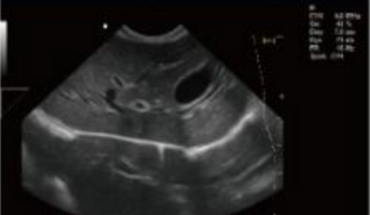

- Equipped with a Wide Range of Probes for Abdominal, Obstetric, Vascular, Cardiac, Small Organ, Urinary Applications

Rich Clinical Application Function